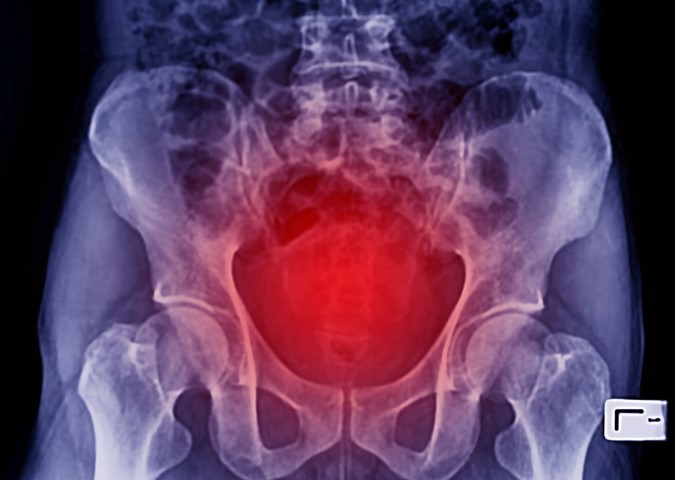

Ask any woman who has experienced one in the past, a pelvic organ prolapse is no laughing matter. The term pelvic organ prolapse describes a condition in which one of the organs in a woman’s pelvic area loses its position and begins to drop toward or into the vaginal area. Different prolapses can affect different organs and vary in severity. To help women gain a better understanding of this condition and its effects, our reproductive healthcare experts have answered a few common questions about pelvic organ prolapse.

The three most prominent forms of pelvic organ prolapse are cystocele, rectocele, and uterine prolapse. A cystocele, the most common form of prolapse, describes when the bladder drops into or out of the vagina. A rectocele refers to any prolapse that affects the rectum. A uterine prolapse (dropped uterus) can sometimes be associated with a small bowel prolapse known as an enterocele.

The most common cause of pelvic organ prolapse is pregnancy and vaginal childbirth, during which the pelvic floor muscles may begin to weaken. Other potential causes of pelvic support issues may include menopause, aging, and physical strain related to heavy lifting. Being overweight or obese can contribute as well due to creating additional pressure on the abdomen and pelvic area. Chronic coughing can also cause a prolapse in some cases.